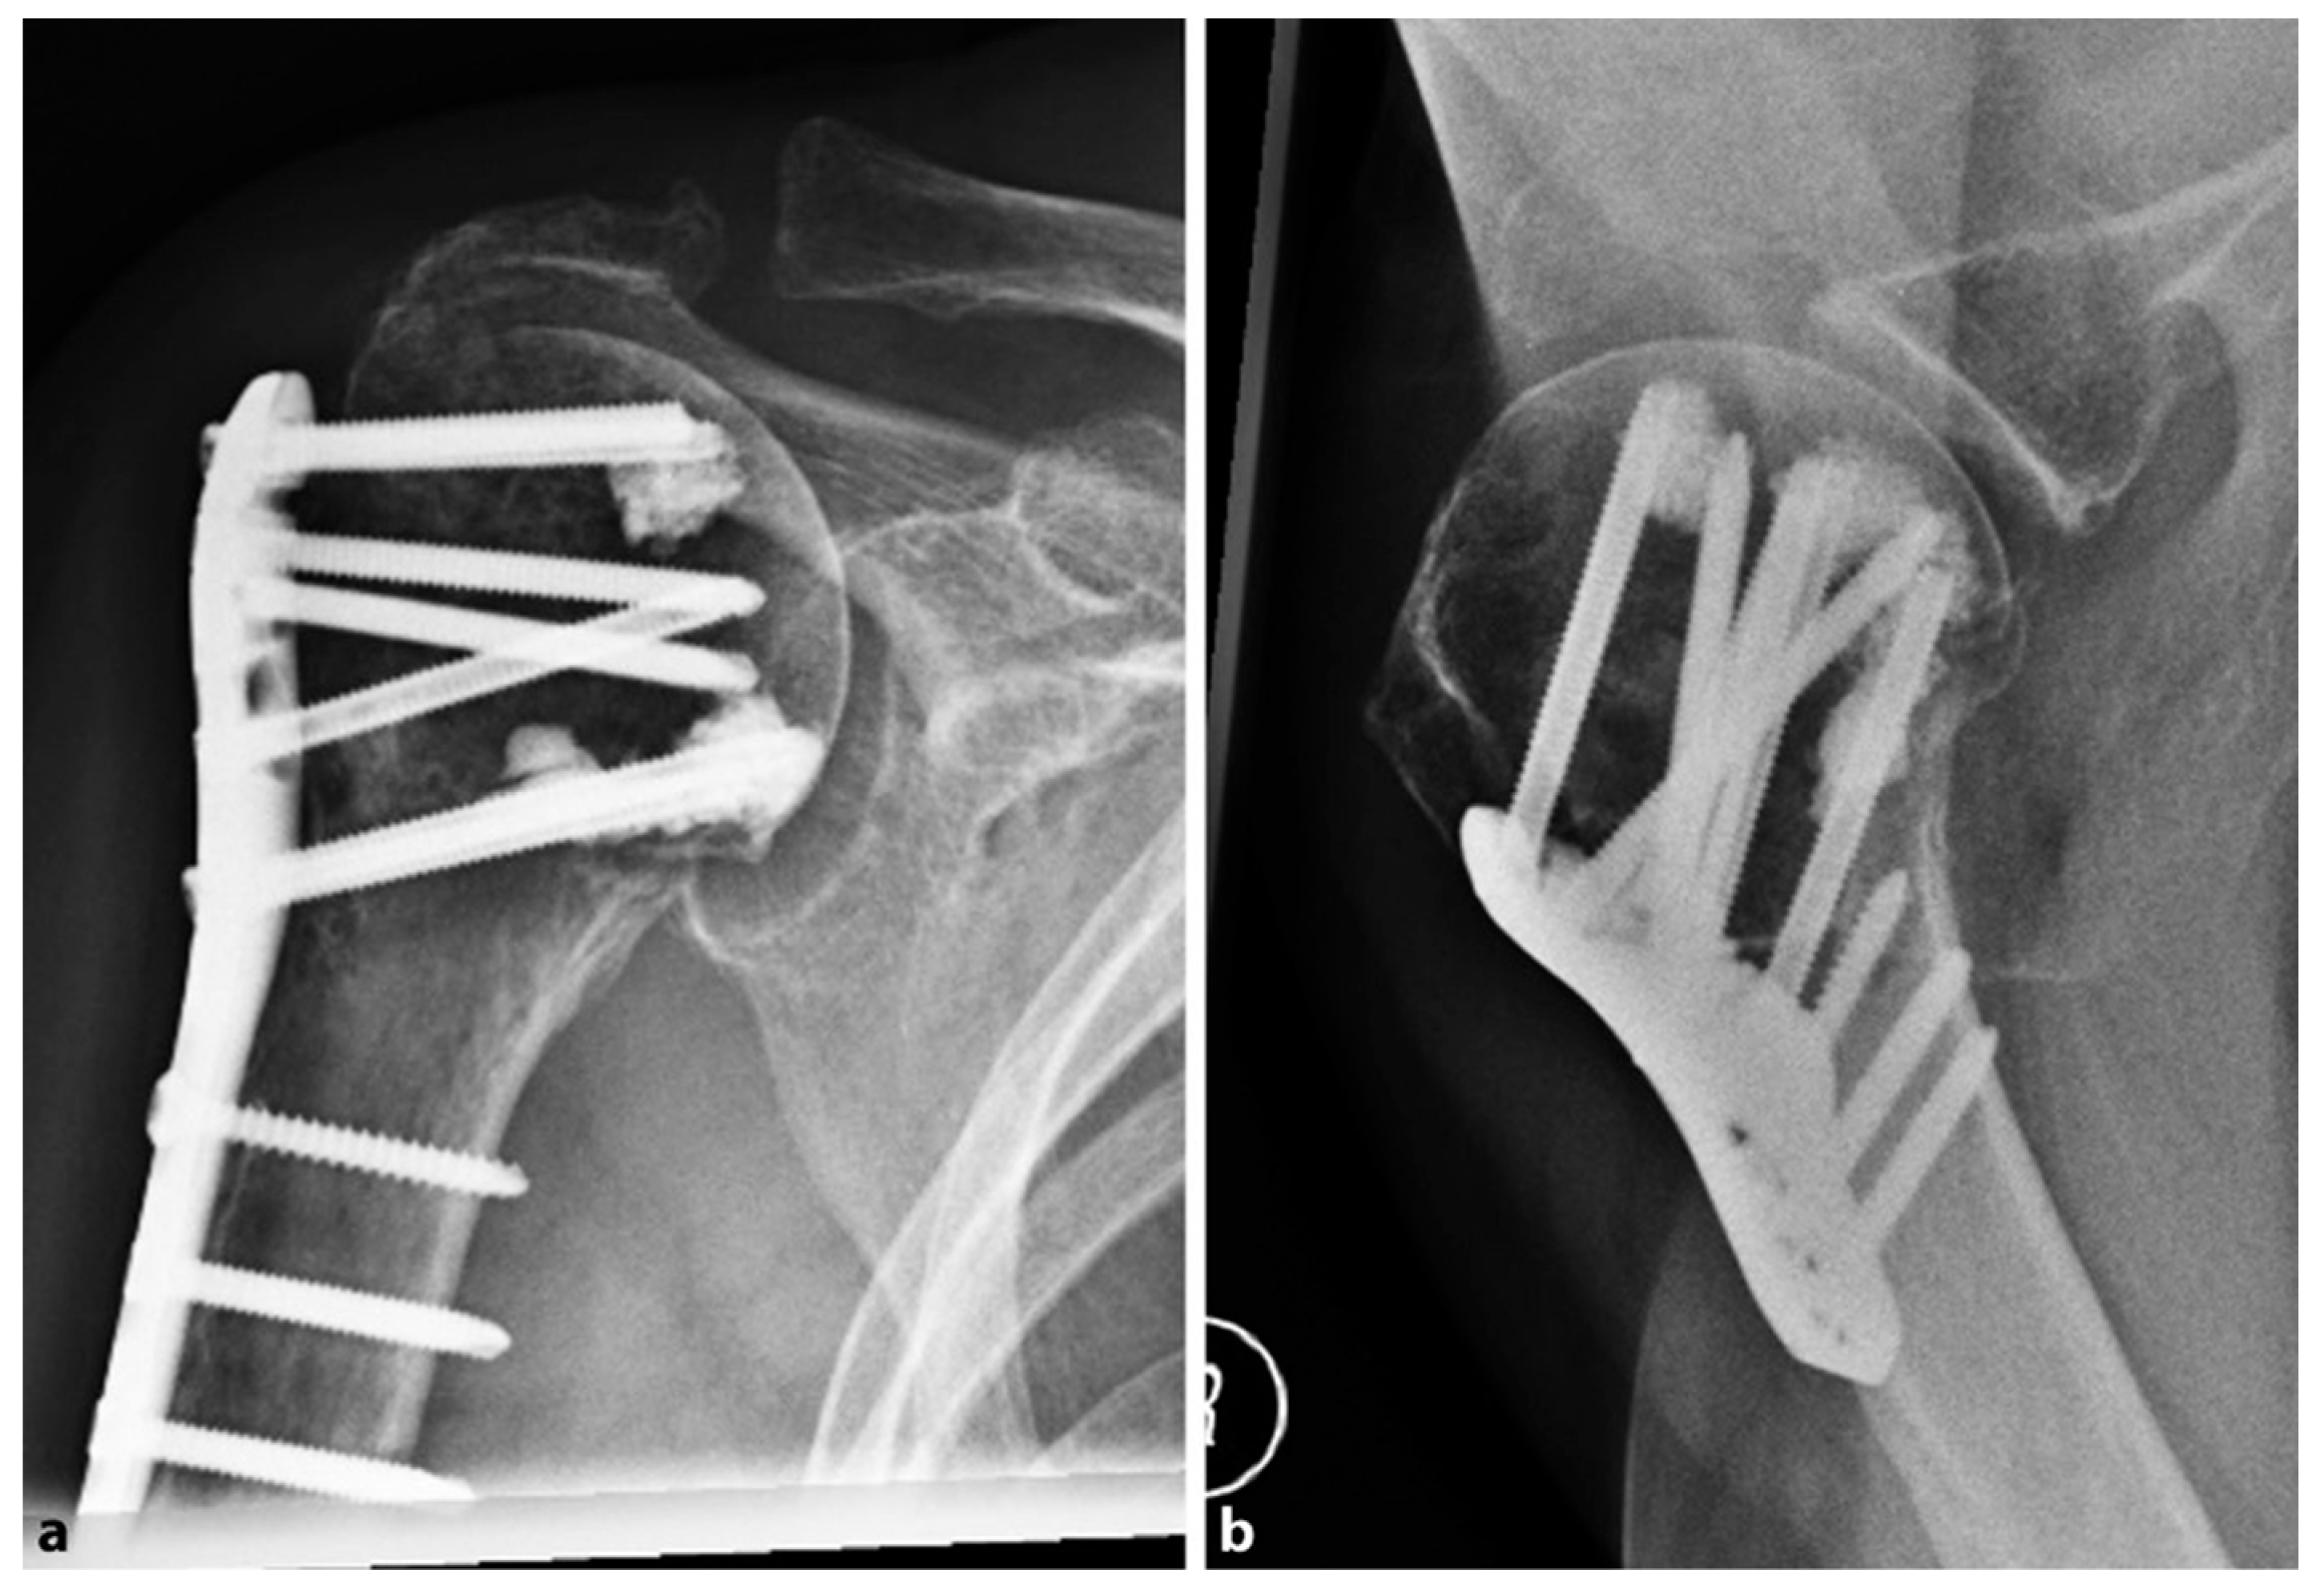

In 2018, Katthagen et al. [30] prospectively treated 24 proximal humeral fractures with the PHILOS plate (DepuySynthes, West Chester, PA, USA) and additional humeral head screw augmentation with PMMA (Figure 2).

Figure 2. Postoperative radiographs of an 87-year-old female patient after locked plating of a proximal humeral fracture with additional cement augmentation of the anterosuperior and inferior humeral head screws: (a) anteroposterior view; (b) axillary view. Credit: Figure 3 from Kattaghen et al. [30] http://creativecommons.org/licenses/by/4.0/.

At the follow-up, no screw penetration was reported. The authors compared the results of 24 fractures derived from a historic retrospective cohort of patients, matched for gender, sex, and type of fracture, who received the conventional PHILOS plate without cementation. In the non-augmented group, four patients (16.6%) suffered screw penetration after the first 6 months, with a significantly increased risk of early loss of reduction (p = 0.037). In the augmented group, no implant-related complications were observed, but two patients (8%) had major biological complications (one avascular necrosis of the humeral head and one nonunion). After 12 months, the mean constant score was 72.9 ± 18.1 points in the PMMA-augmented group and 73.0 ± 13.1 points in the non-augmented group (0.557), with no significant differences observed (p = 0.62).